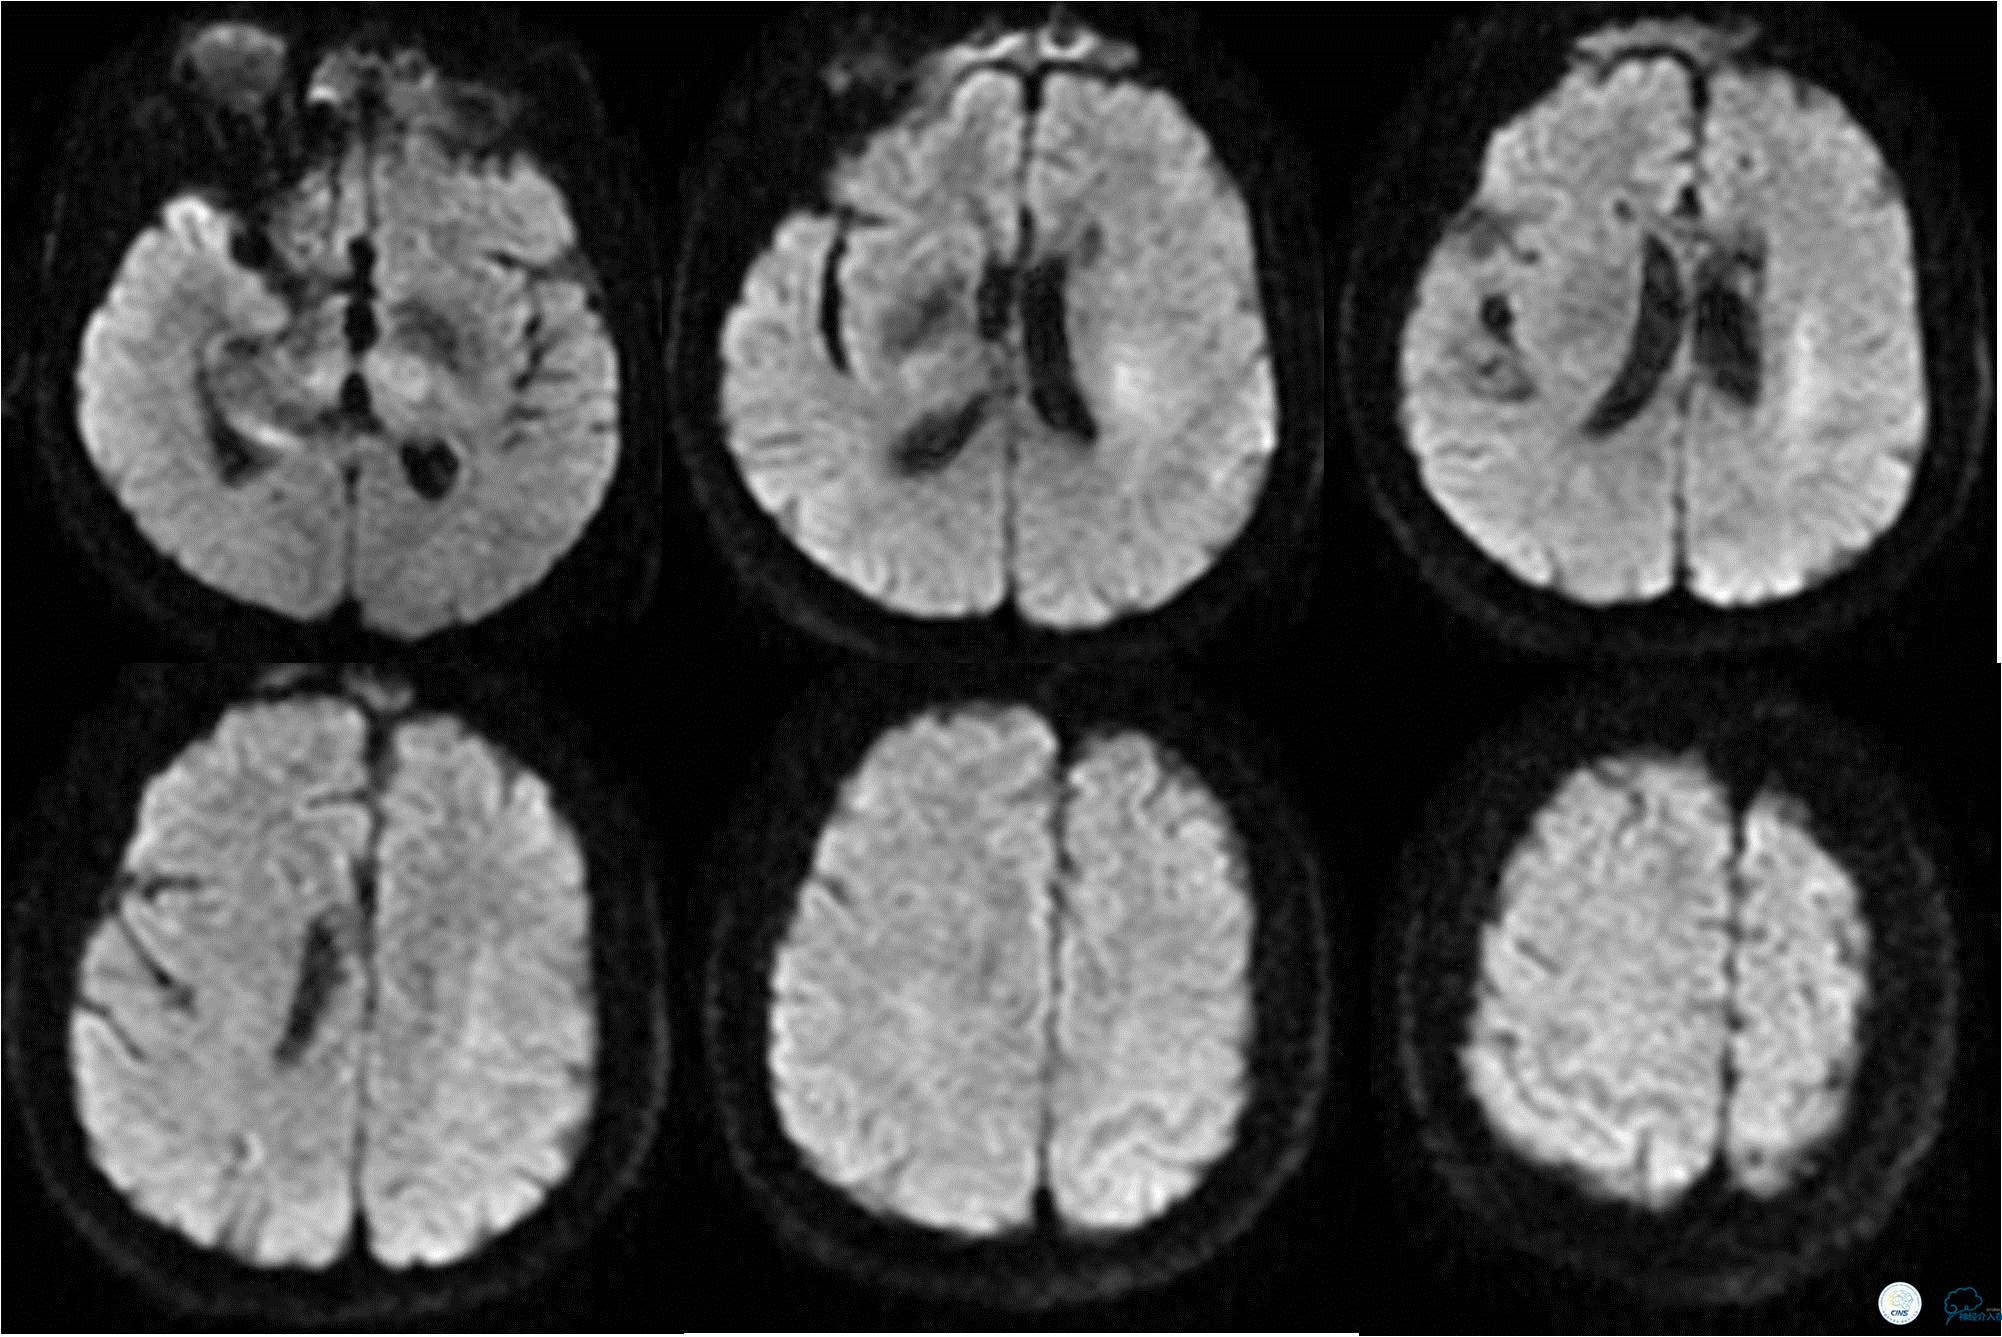

》术后10天,复查MRI